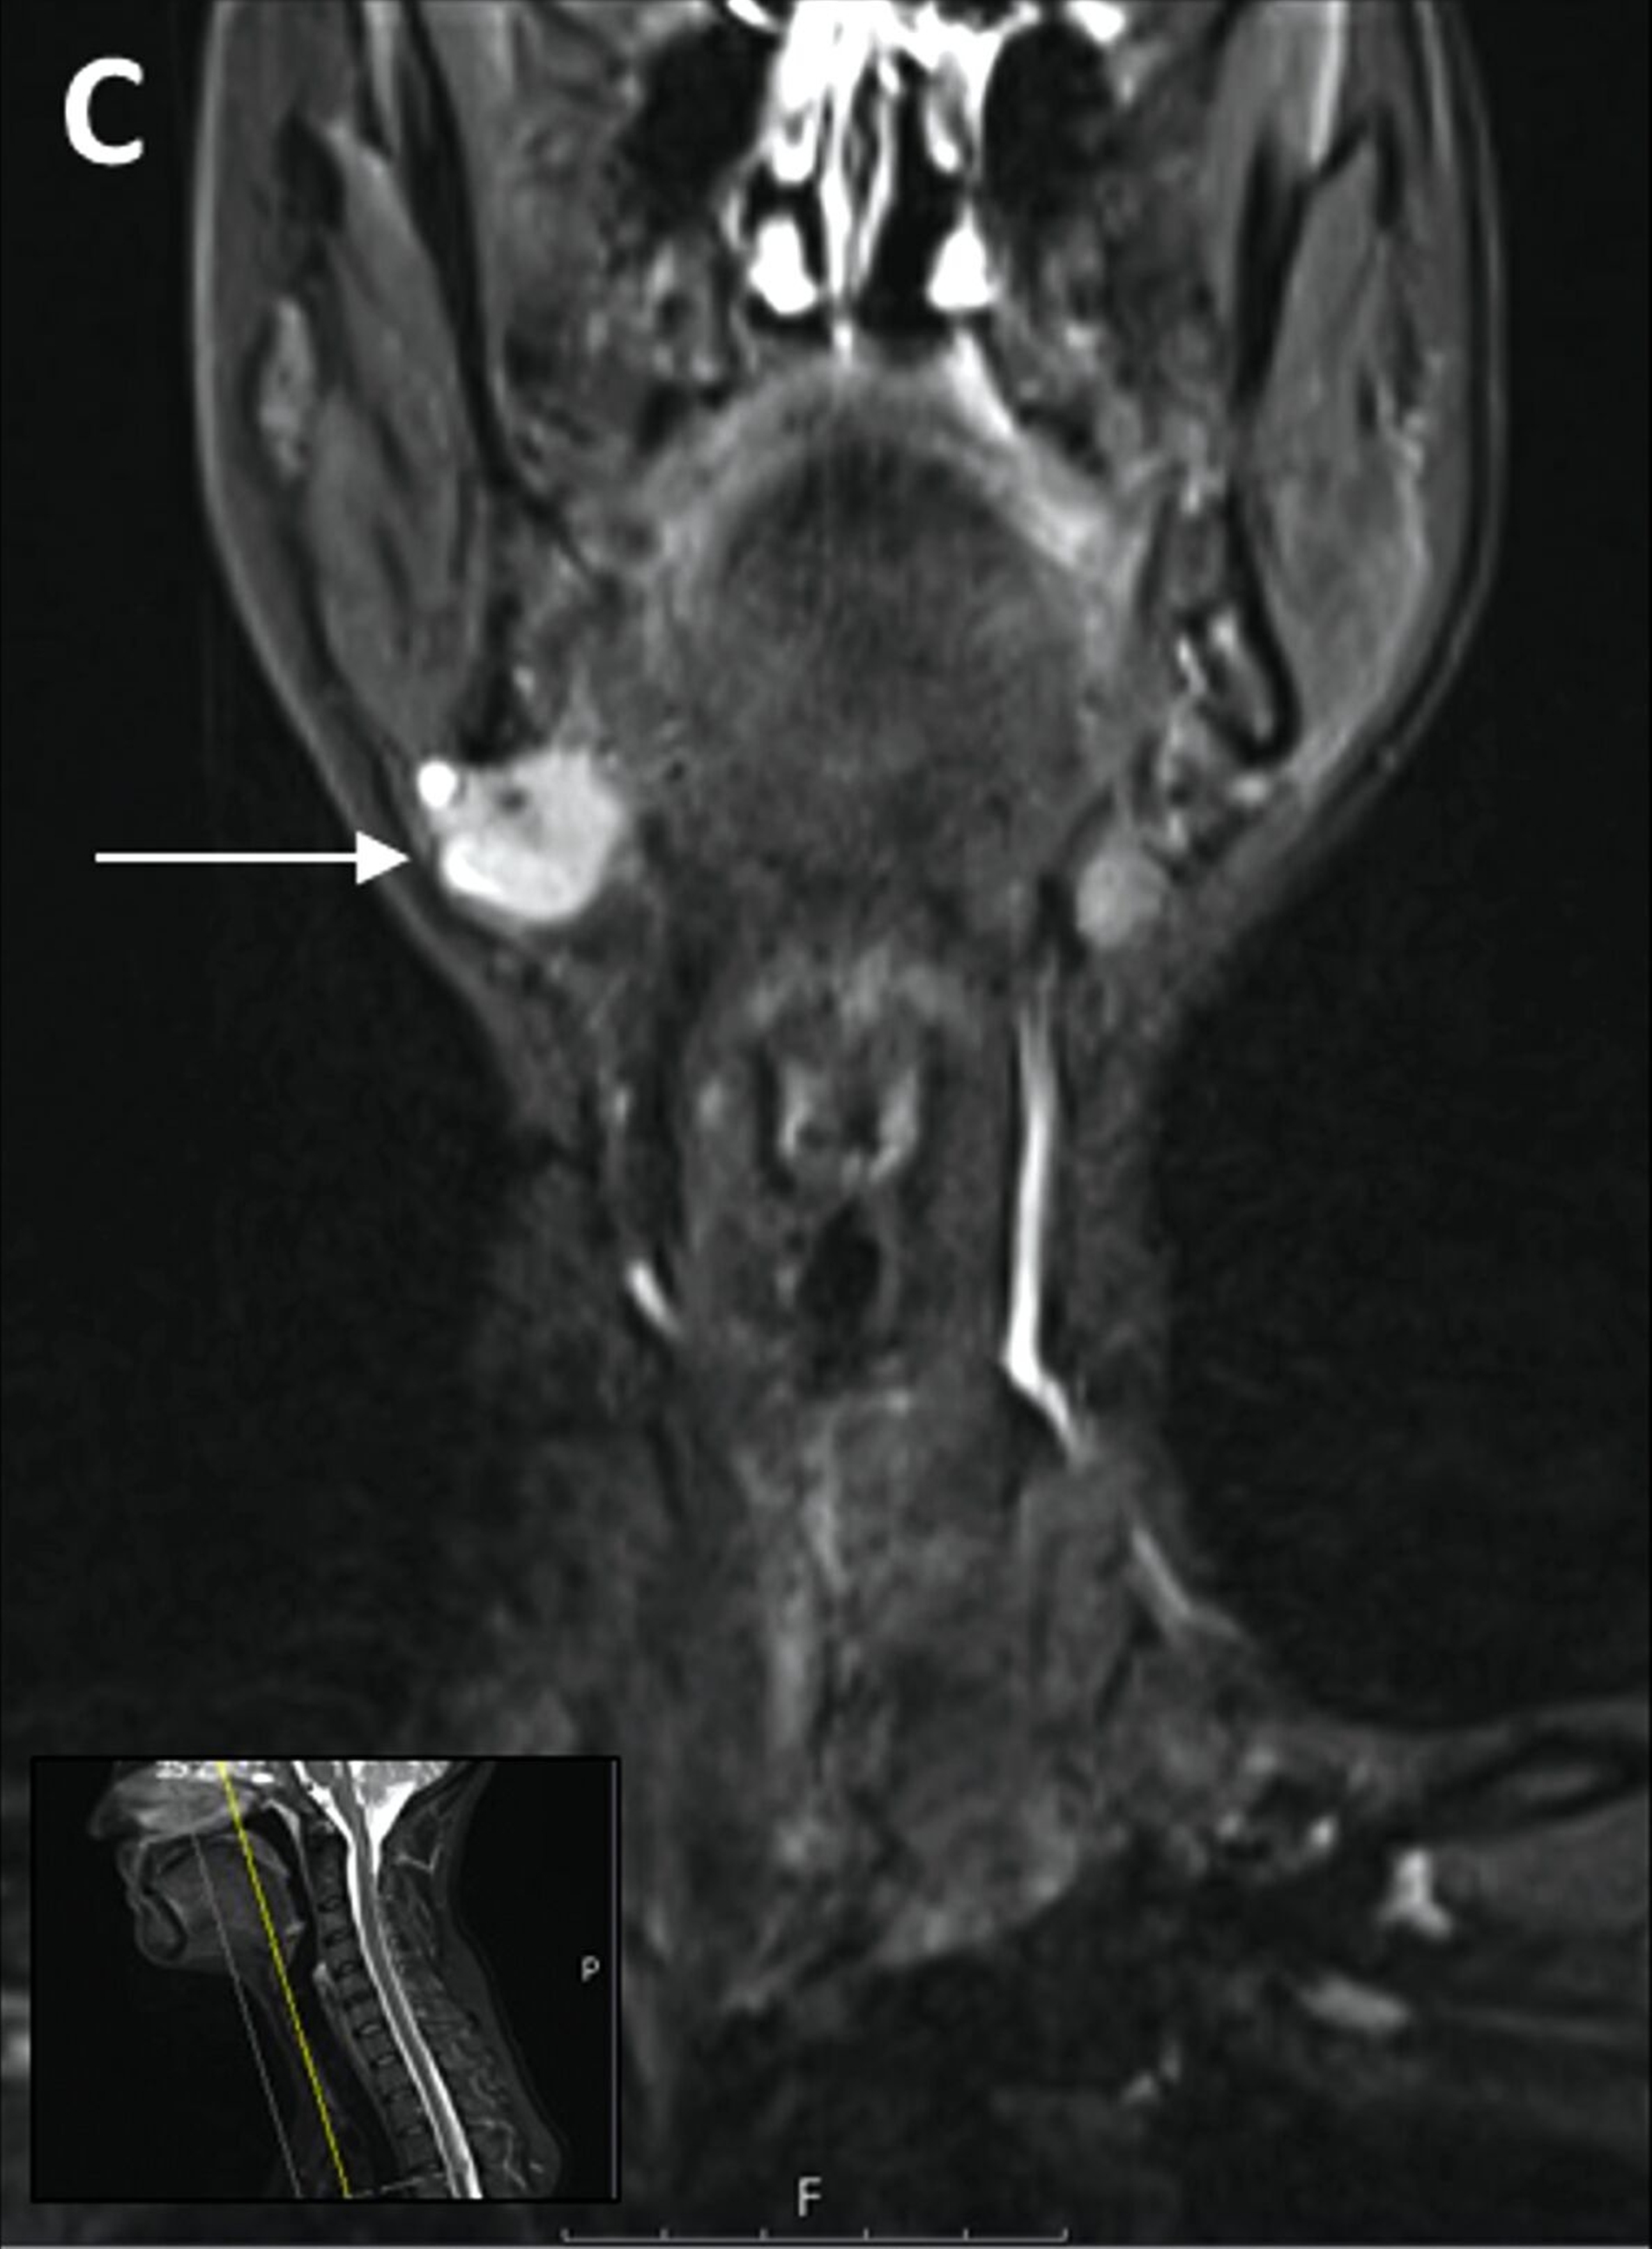

Trotz vorübergehender Remission kam es im August 2023 zu einem erneuten Krankheitsfortschritt mit dem Auftreten eines Metastasen-suspekten Lymphknotens im rechten Halsbereich (Abbildung 1). Bei der chirurgischen Entfernung (Abbildung 2) sowie der histologischen und molekularpathologischen Untersuchung wurde ein kleinzelliges neuroendokrines Lungenkarzinom nachgewiesen (Abbildung 3). Zusätzlich wurden genetische Analysen durchgeführt, die verschiedene Genmutationen und eine Fusion von CTNND1:KMT2A ergaben. Die Therapieentscheidungen basieren derzeit auf den Ergebnissen der molekularen Tumorboarddiskussion.